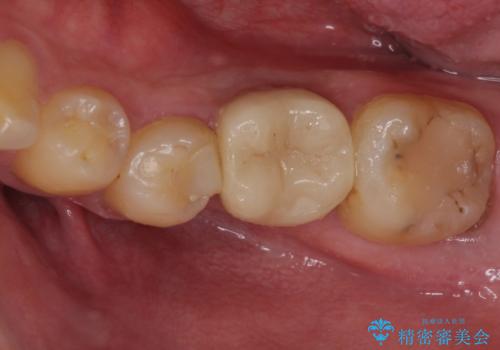

セラミッククラウンによる奥歯のむし歯治療

- 奥歯がしみて痛いとのことで来院された患者様です。

既に複数箇所の修復が行われていたため、オールセラミッククラウンにて補綴をすることとしました。

以前装着した修復物が不適であり、歯肉が腫れていましたが、仮歯を装着したことで腫れは解消されました。

歯の痛みだけでなく、歯肉の腫れも改善され、患者様には大変満足していただきました。